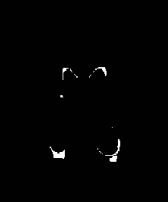

The white matter lesions in a total of 15 subjects were manually delineated by a neuroradiologist to be used as ground truth lesion segmentations for evaluation of the proposed method. We compared the proposed method with three state-of-the-art segmentation methods: 1) A supervised tissue segmentation developed for the AGES-Reykjavik data set, created with an artificial neural network classifier in the four dimensional intensity space defined by FLAIR, T1-w, T2-w and Proton Density weighted images and trained on 11 manually annotated subjects[12]; 2) the patch-based Subject Specific Sparse Dictionary Learning (S3DL) method [19], which takes FLAIR and T1-weighted images as input for lesion segmentation as well as three manually annotated atlases; and 3) the whole brain segmentation method FreeSurfer [17], which only takes a T1-weighted image as input, but is included in the comparison due to its widespread use. For each of the methods above, the preprocessing steps were as described in their associated publications. A visual comparison of the methods is shown for two subjects in Figure 2. The top row in Figure 2 demonstrates that SegAE can accurately segment lesion boundaries of the test image with the largest lesion load. The bottom row shows an example of a subject with a smaller lesion load but with enlarged ventricles.

| FLAIR image | Supervised | FreeSurfer | S3DL | SegAE | Manual |

|---|---|---|---|---|---|

![]() |